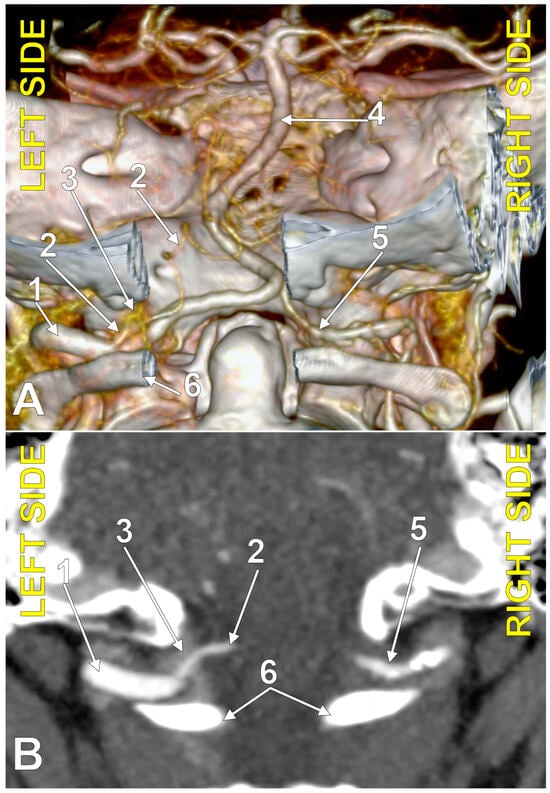

4.7. The Bihemispheric PICA

4.8. The Caudal Loop of the PICA